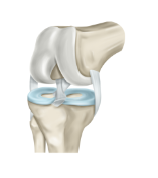

무릎 인공관절이란, 무릎 관절의 손상이나 결손으로 인해 기능이 손상된 환자들에게 수술적인 개입을 통해 삽입되는 인공적으로 만들어진 관절입니다. 인공 관절은 대개 금속, 플라스틱, 세라믹 등으로 만들어지며, 퇴행성 관절질환, 골관절염, 골절, 연골손상 등의 경우에 수술적인 개입을 통해 적용됩니다. 무릎 인공관절 수술은 보통 전체마취를 사용하며, 인공 관절을 무릎 관절에 적용하는 방법은 다양합니다. 수술 후에는 치료 과정이 필요하며, 치료 후에는 신체 활동의 제한이나 운동 요법 등이 필요합니다. 그러나 수술적인 위험성과 치료 후에도 부작용이 발생할 수 있으므로, 수술 전에 신중하게 검토하고 진행하는 것이 중요합니다.

무릎 인공관절 수술 절차

1. 전신마취 또는 척추마취를 통해 환자의 의식을 잃게 합니다.

2. 무릎 관절 부위를 절개하여 피부와 근육을 젖힙니다.

3. 손상된 연골과 뼈를 제거하고 인공관절을 적합한 위치에 고정합니다.

4. 젖힌 피부와 근육을 복원하고 봉합합니다.

5. 수술 부위에 압박붕대를 감아 출혈을 막습니다.